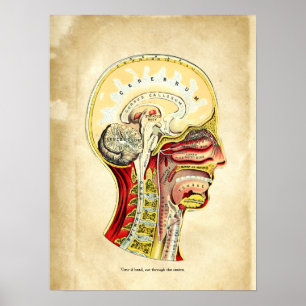

Vintage Illustration Human System Poster

PriceCA$52.05